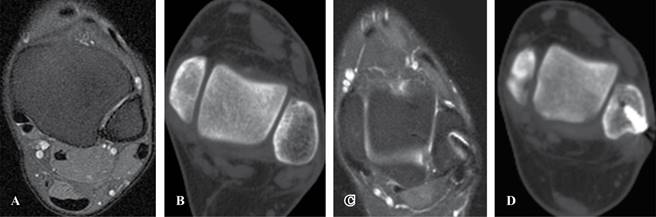

Se realizó un estudio retrospectivo de cinco pacientes con diagnóstico clínico-imagenológico de luxación crónica y sintomática de los tendones peroneos intervenidos quirúrgicamente (Figura 1). Todos los pacientes fueron del sexo masculino, jóvenes deportistas recreacionales y con un promedio de edad de 30 años.

Figura 1: A) Resonancia magnética nuclear, subluxación del tendón peroneo. B) Tomografía axial computada donde se evidencia la convexidad del surco retro-maleolar. C) Resonancia magnética nuclear seis meses postoperatorios y reducción del tendón peroneo. D) Profundización del canal retro-maleolar.

Los resultados clínicos se evaluaron mediante el score AOFAS (American Orthopaedic Foot and Ankle Society) en el preoperatorio y a 18 meses de postoperatorio; los pacientes fueron comparados utilizando el test de Welch, y el nivel de significancia fijado fue en p < 0.05. Los resultados en las imágenes se evaluaron mediante resonancia magnética nuclear (RMN) sin contraste, ecografía dinámica y tomografía axial computada (TAC) sin contraste, en forma preoperatoria y a 18 meses de forma postoperatoria. También se tuvo en cuenta el momento del retorno a su actividad deportiva previa. El seguimiento promedio fue de 26.3 meses.

Los resultados imagenológicos fueron evaluados a 18 meses del postoperatorio. En un paciente se visualizó en la resonancia magnética por imágenes un engrosamiento del tendón del peroneo lateral corto, el cual fue interpretado como un engrosamiento del tendón por reparación del mismo. En dos pacientes se reconoció en la tomografía axial computada postoperatoria una insuficiente profundización del surco retromaleolar peroneo, sin implicancias clínicas. En ningún paciente se apreció desgarro en la resonancia magnética postoperatoria. Ningún paciente presentó subluxaciones evidenciables mediante ecografías dinámicas.